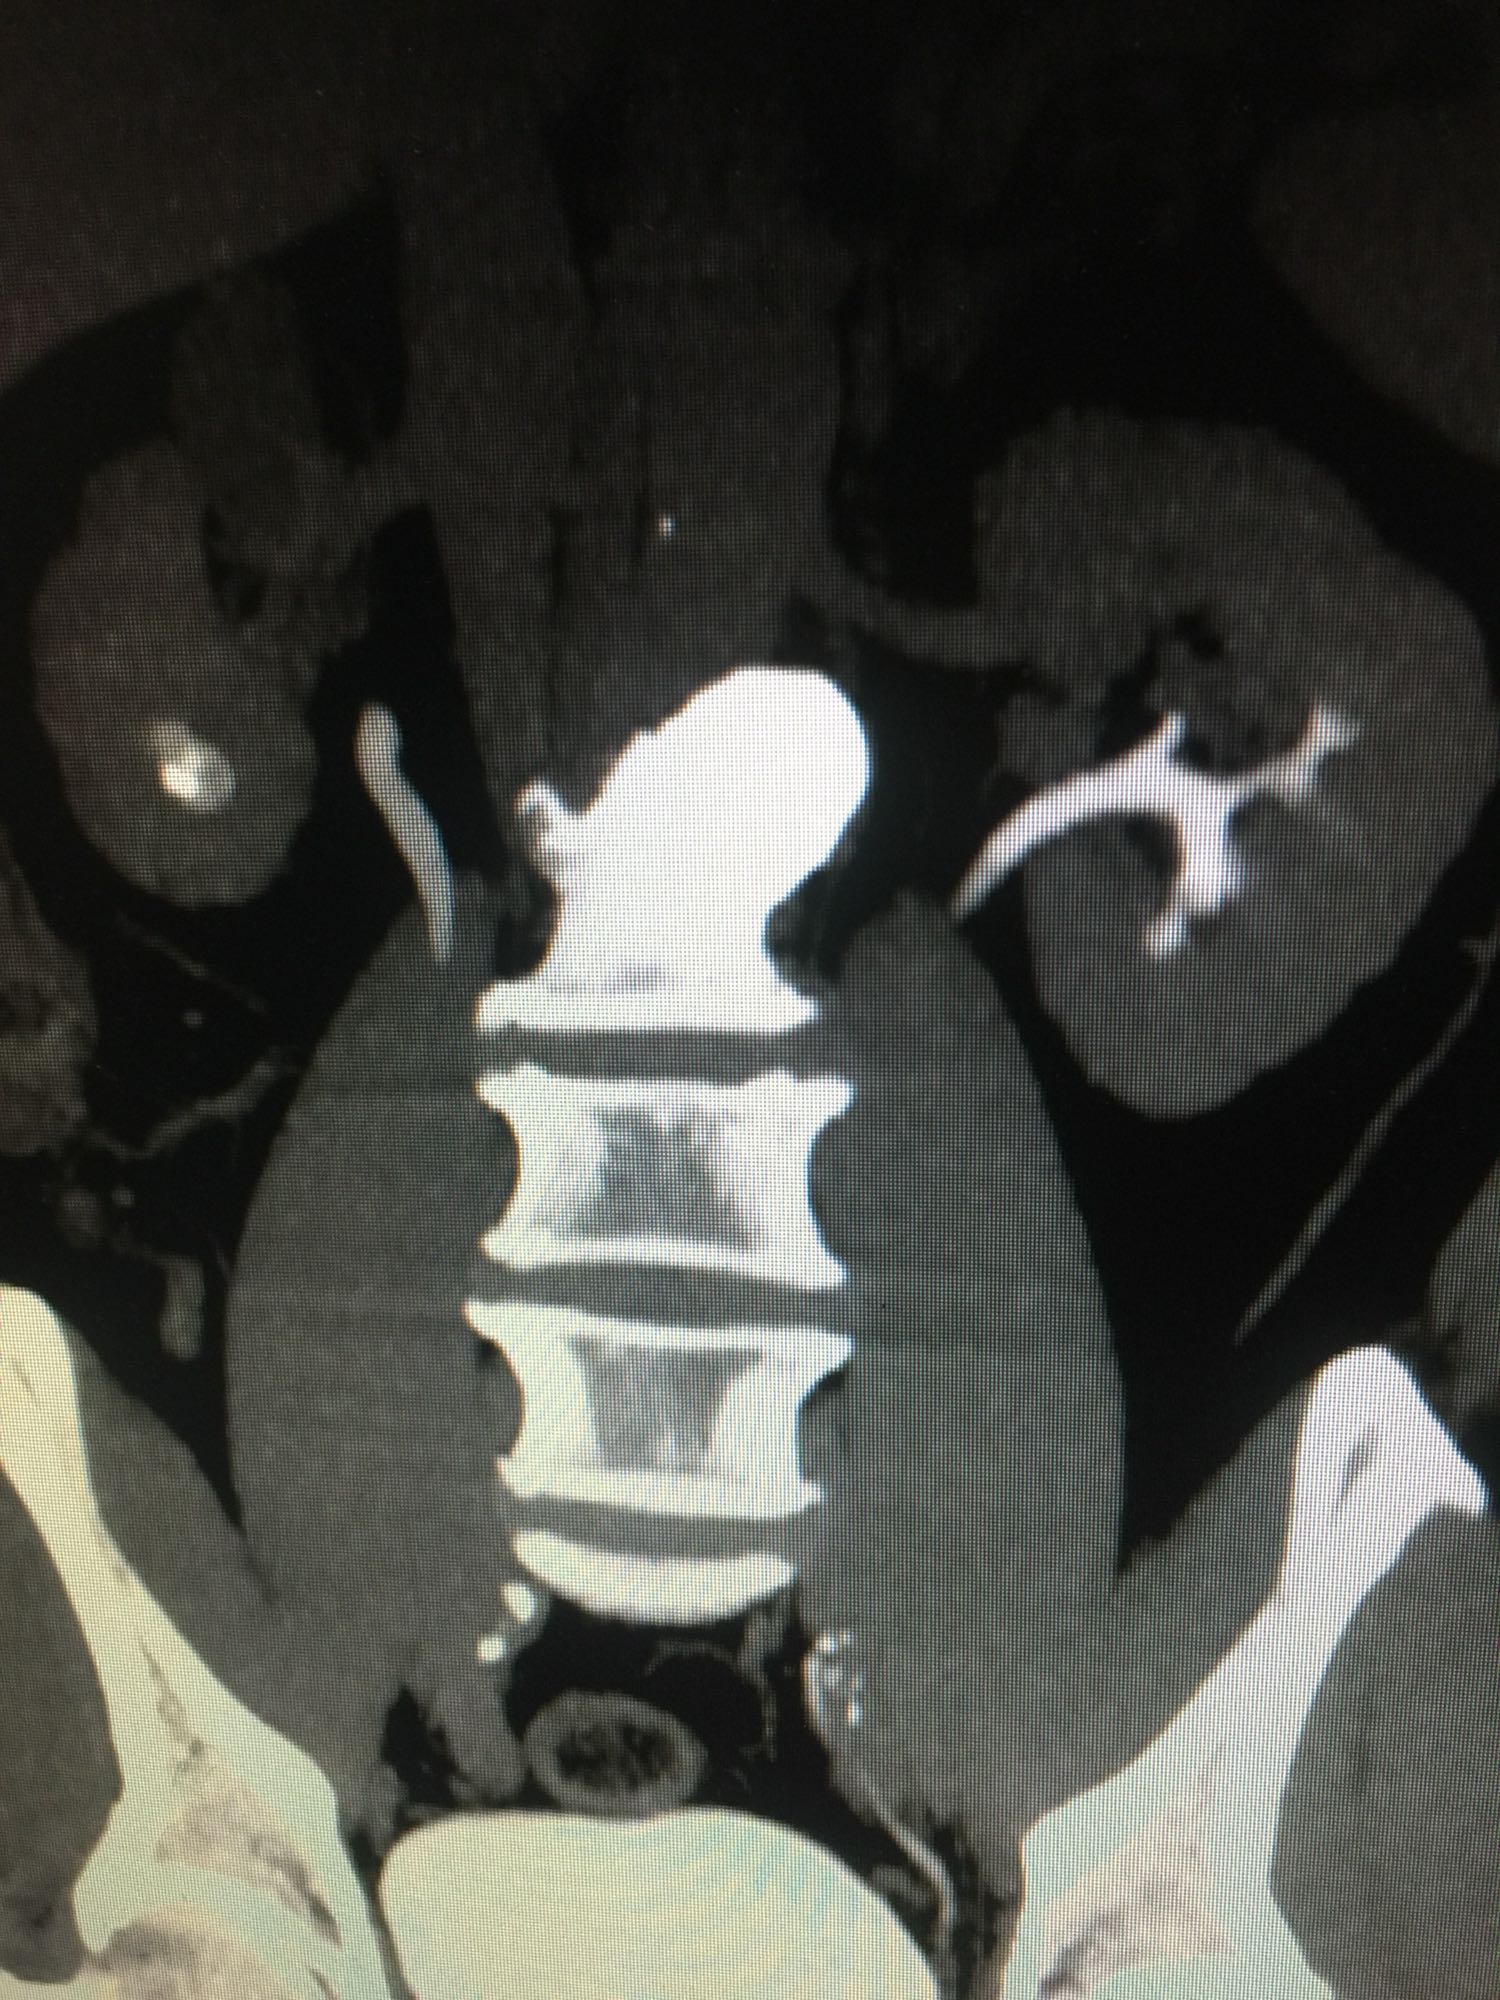

查体:双肾区无叩压痛,膀胱区无叩压痛,无叩浊,前列腺二度,质地中等,无压痛,无结节。CTU提示右肾铸型结石。ECTL 40,R14.5

右肾铸型结石 予以经皮肾碎石治疗,术后复查平片未见结石残留。